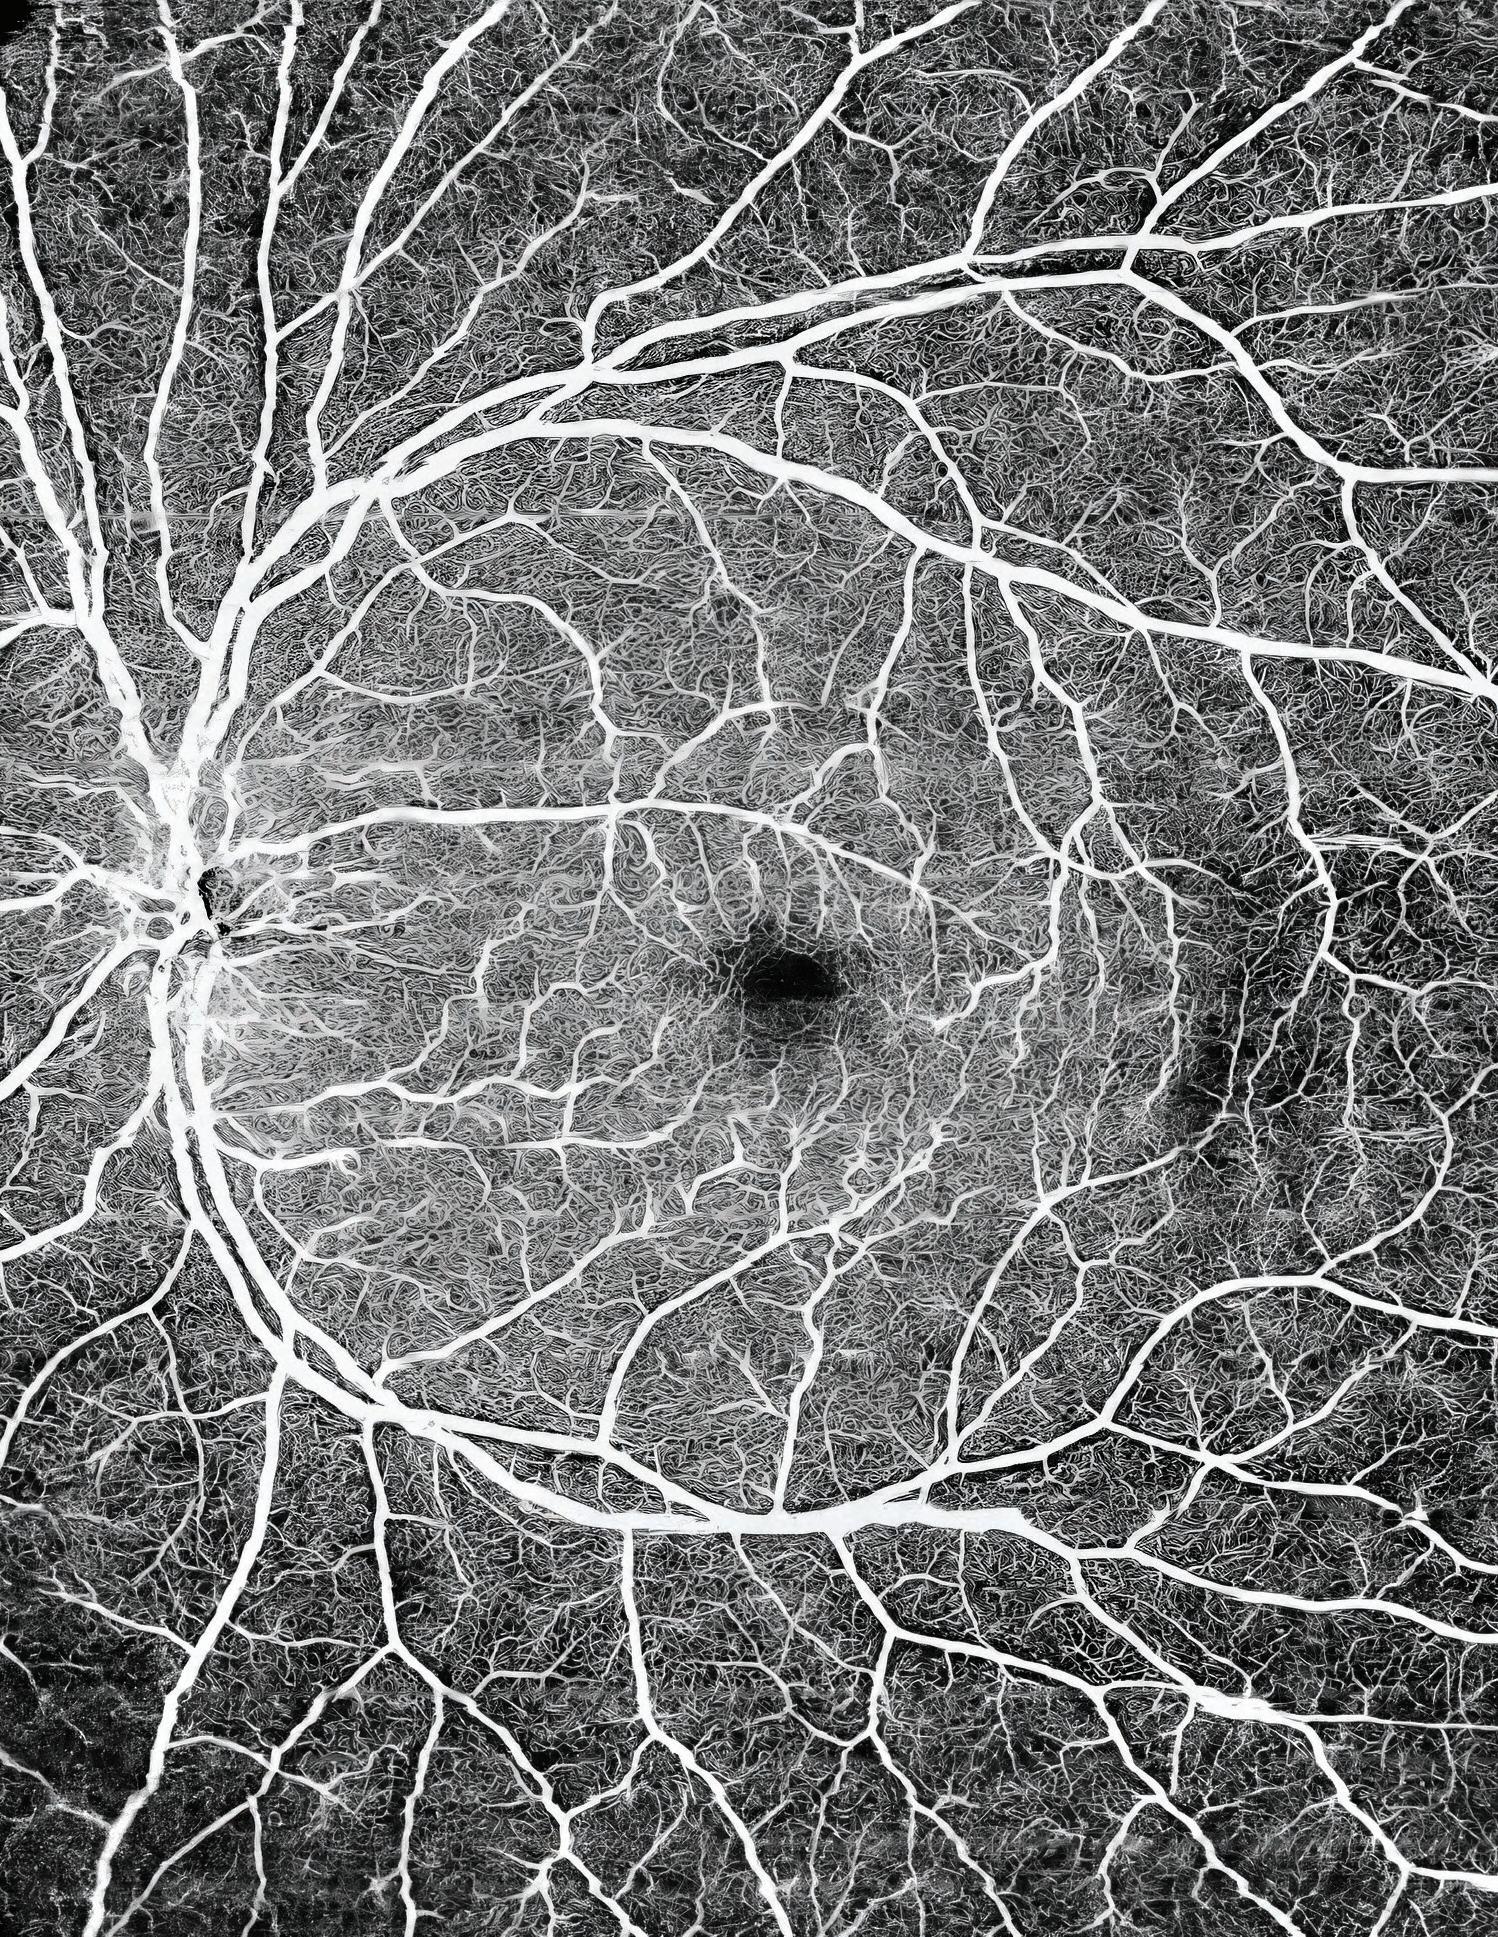

Alon Harris, MS, PhD, FARVO, Professor of Ophthalmology, and Artificial Intelligence and Human Health at the Icahn School of Medicine at Mount Sinai, has spent much of his career studying the impact of vascular and cardiovascular risk factors on the development and progression of glaucoma. A new study he helped pilot combines optical coherence tomography angiography (OCTA) and artificial intelligence (AI) to offer the strongest evidence yet for considering both vascular and structural variables in characterizing and assessing POAG risk in humans.

The novel study used neural network machine learning models trained on specific datasets to identify biomarkers that could prove most useful in understanding the etiology of the disease for which no gold standard, especially in its earliest stages, currently exists. Above all, the team learned that OCTA vascular parameters were equal to or better than OCT-assessed structural endpoints, including retinal nerve fiber layer, ganglion cell complex, and macular thickness for predicting risk for early-stage glaucoma.

“OCT structural measures, including retinal nerve fiber layer and ganglion cell complex thickness, have long been used for diagnosing and characterizing glaucoma, but our paper shows that OCTA vascular parameters may have the same diagnostic strength, and should therefore be actively investigated,” explains Dr. Harris, co-author of the study and Co-Director of the Barry Family Center for Ophthalmic Artificial Intelligence and Human Health at the Icahn School of Medicine. “Our data also suggest that POAG predictability may not only be enhanced through OCTA-identified biomarkers, but that these could be highly informative to clinicians at the earliest stages of the disease, before significant visual field loss occurs.”

The New York Eye and Ear Infirmary of Mount Sinai (NYEE) study, published in the September 2024 issue of Investigative Ophthalmology & Visual Science , used small artificial neural network models, also known as multi-layer perceptrons, that were trained on datasets comprising 144 POAG patient eyes and 149 controls without eye disease. The analysis showed that AI models trained with OCTA measurements performed similarly to models that used OCT structural markers for diagnosis. Interestingly, combining OCT and OCTA measurements into one model did not improve the results, suggesting to the team that both imaging modalities provide similar information about glaucoma through different formats.

According to lead author Nicholas Riina, a medical student for the past two years in Dr. Harris’s lab, the observational study was particularly successful in using AI and minimally invasive OCTA to explore where few researchers had been before: the hemodynamics, or blood flow, within the microvasculature of the eye. “Leveraging these technologies gave us a highresolution window on hemodynamic factors of the eye, such as changes to blood vessel density in the retina, allowing us to compare them to the more established structural parameters gathered through OCT,” Mr. Riina says.